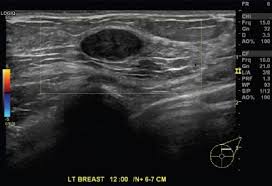

What Does Inflammatory Breast Cancer Look Like On Ultrasound / Benign And Malignant Characteristics Of Breast Lesions At Ultrasound Radiology Reference Article Radiopaedia Org : Ultrasound is useful for looking at some breast changes, such as lumps (especially those that can be felt but not seen on a mammogram) or changes in women with dense breast tissue.. Unlike typical breast cancer, ibc usually cannot be detected by a mammogram or ultrasound. What does breast cancer look like on a mammogram? Inflammatory carcinoma of the breast, also referred to as inflammatory breast cancer, is a relatively uncommon but aggressive form of invasive breast carcinoma with a characteristic clinical presentation and unique radiographic appearances. I need some knowledge about ibc. My last breast ultrasound was december.

Early warning signs of inflammatory breast cancer along with images of inflammatory breast cancer are mentioned below. Does this look like inflammatory breast cancer? Unlike typical breast cancer, ibc usually cannot be detected by a mammogram or ultrasound. Ultrasounds are useful for detecting signs of breast cancer even after a mammogram comes back negative. Googled and freaking out about ibc. The usual cause of inflammatory breast symptoms is breast mastitis or duct ectasia. The breast tissue deflects these waves causing echoes, which a computer uses to paint a picture of what's going on inside the breast tissue (no radiation is involved). In view of those symptoms often occur, and errors in diagnosis of patients treated for inflammatory diseases, that happen to be named and are known as these forms breast cancer.

Did not respond to antibiotic and was referred for biopsy. Inflammatory breast cancer is often misdiagnosed because it is so rare, and is difficult to treat because it is particularly aggressive. What does breast cancer look like on a mammogram? However, inflammatory breast cancers are more likely to show solid mass lesions. My last breast ultrasound was december. As these inflammatory breast cancer picture shows, the texture of the breast may change and appear to look dimpled or ridged, like an orange peel. The woman who has inflammatory breast cancer has breast cancer that's red and inflamed, with an angry look to the breast cancer, he says. The problem is that inflammatory breast cancer can look very much like mastitis early on, and is often diagnosed only after a woman has been treated first for mastitis (often with no improvement in symptoms). What does breast cancer look like? I need some knowledge about ibc. These tubes, which are hollow, allow lymph fluid to drain out of the breast. I have inflammatory breast cancer which was firstly diagnosed as mastitis in jan 09. Women or men who develop any of the inflammatory breast cancer early signs should seek medical care immediately to ensure timely treatment.

These tubes, which are hollow, allow lymph fluid to drain out of the breast. The problem is that inflammatory breast cancer can look very much like mastitis early on, and is often diagnosed only after a woman has been treated first for mastitis (often with no improvement in symptoms). Kathleen ruddy inflammatory breast cancer accounts for approximately 5% of all cases of invasive breast cancer in the united states. Inflammatory breast cancer is often misdiagnosed because it is so rare, and is difficult to treat because it is particularly aggressive. A small red spot that looks very much like an insect bite or rash can be an early sign of ibc. Because ibc grows quickly, it is usually found at a locally advanced stage, meaning that cancer cells have spread into nearby breast tissue or lymph nodes. Googled and freaking out about ibc. The woman who has inflammatory breast cancer has breast cancer that's red and inflamed, with an angry look to the breast cancer, he says. Online says it develops suddenly. However, these signs and symptoms are most often associated with benign breast conditions. Inflammatory breast cancer (ibc) is rare, making up about 2 to 4 percent of breast cancer cases. Other ultrasound findings that suggest breast cancer include: The breast tissue deflects these waves causing echoes, which a computer uses to paint a picture of what's going on inside the breast tissue (no radiation is involved).